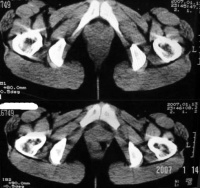

3.CT表现:

(1)输卵管积液或输卵管卵巢囊肿在大多数病例中不能与其他囊性肿块鉴别。

(2)输卵管-卵巢脓肿直径需>2cm以上CT才易于显示,表现为混杂密度肿块,边缘光滑或有毛刺,壁厚而不规则,脓肿壁在增强后比一般囊肿有更明显的强化。当囊内有气体存在时,对诊断脓肿有帮助。

(3)积液时CT值为0~15HU,积脓时CT值为15~40HU。